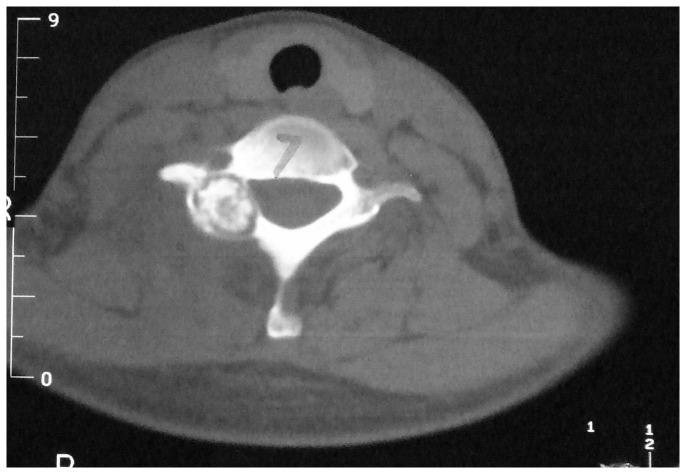

From June 2006 to July 2011, 18 patients with spinal osteoblastoma treated surgically were analyzed retrospectively. There were 11 males and 7 females with an average age of 27.5 years(range, 16-38 years). The tumors were located at C5 in 7, C6 in 6, C7 in 3, C6-T1 1 in 1 and T11 in 1. Based on WBB classification, 16 were 1-3 or 10-12 and 2 were 4-9 and 1-3. 18 operations had been performed with en bloc resection. A posterior approach was used for 16 patients, and a combined posterior and anterior approach was used for 2 patients. Reconstruction using instrumentation and fusion was performed using spinal instrumentation in 13 patients. We used visual analogue scales (VAS) to evaluate the change of pain before and after the operation, and the McCormick System to assess functional status of the spine. Imaging test was used to review the stability and recurrence rate of spine cord, and the confluence of graft bones.

All cases were followed up for 24-80 months (average, 38.4 months). The average surgical time was 120.8 minutes (range, 80-220 minutes), with the average intraoperative blood loss of 520 ml (range, 300-1200 ml). During the follow-up period, the VAS grade reduced from 6.46±1.32 to 2.26±1.05 (P <0.05). 15 patients had neurological function improved and 3 remained no change which was evaluated by McCormick scale for spinal function status at final follow-up.

Spinal osteoblastoma has its own specific radiographic features. There is some recurrence in simple curettage of tumor lesion. The thoroughly en bloc resection of tumor or spondylectomy, bone fusion and strong in Ter fixation are the key points for successful surgical treatment.